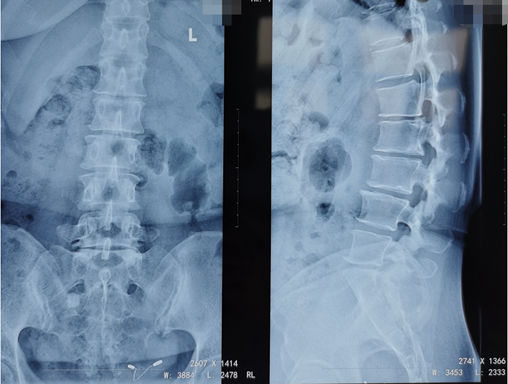

刘大姐来陕西冶金医院神经脊柱科了两次:第一次因为剧烈的腰痛和右腿疼痛,当时她疼得右边腿都抬不起来,走路只能扶墙走,平时活动离不开腰围,检查后发现她的腰5骶1处发生了突出,并严重地压迫、刺激到神经根。这种情况熊东主任建议刘大姐进行微创手术治疗,但是由于惧怕手术,她还是选择了保守治疗,并在神经脊柱科进行了康复理疗,症状缓解后出院。

术前影像学资料